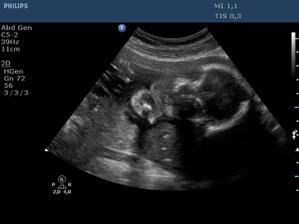

Ultrazvuk miminka - 24 týden

Z "menší protekce" u pana primáře Radiodiagnostického oddělení jsme mohli na soukromou "špionáž" naší krásné holčičky... (Pan doktor je už třetí, kdo hádá holčičku a po pravdě s tím přístrojem, co má k dispozici, bylo naprosto zřetelně vidět, že tam žádný pytlík není! :o)) Natočil nám i několik videí, kde ta naše šibalka zívala a dvakrát na nás dokonce vyplazovala jazyk. ;o)